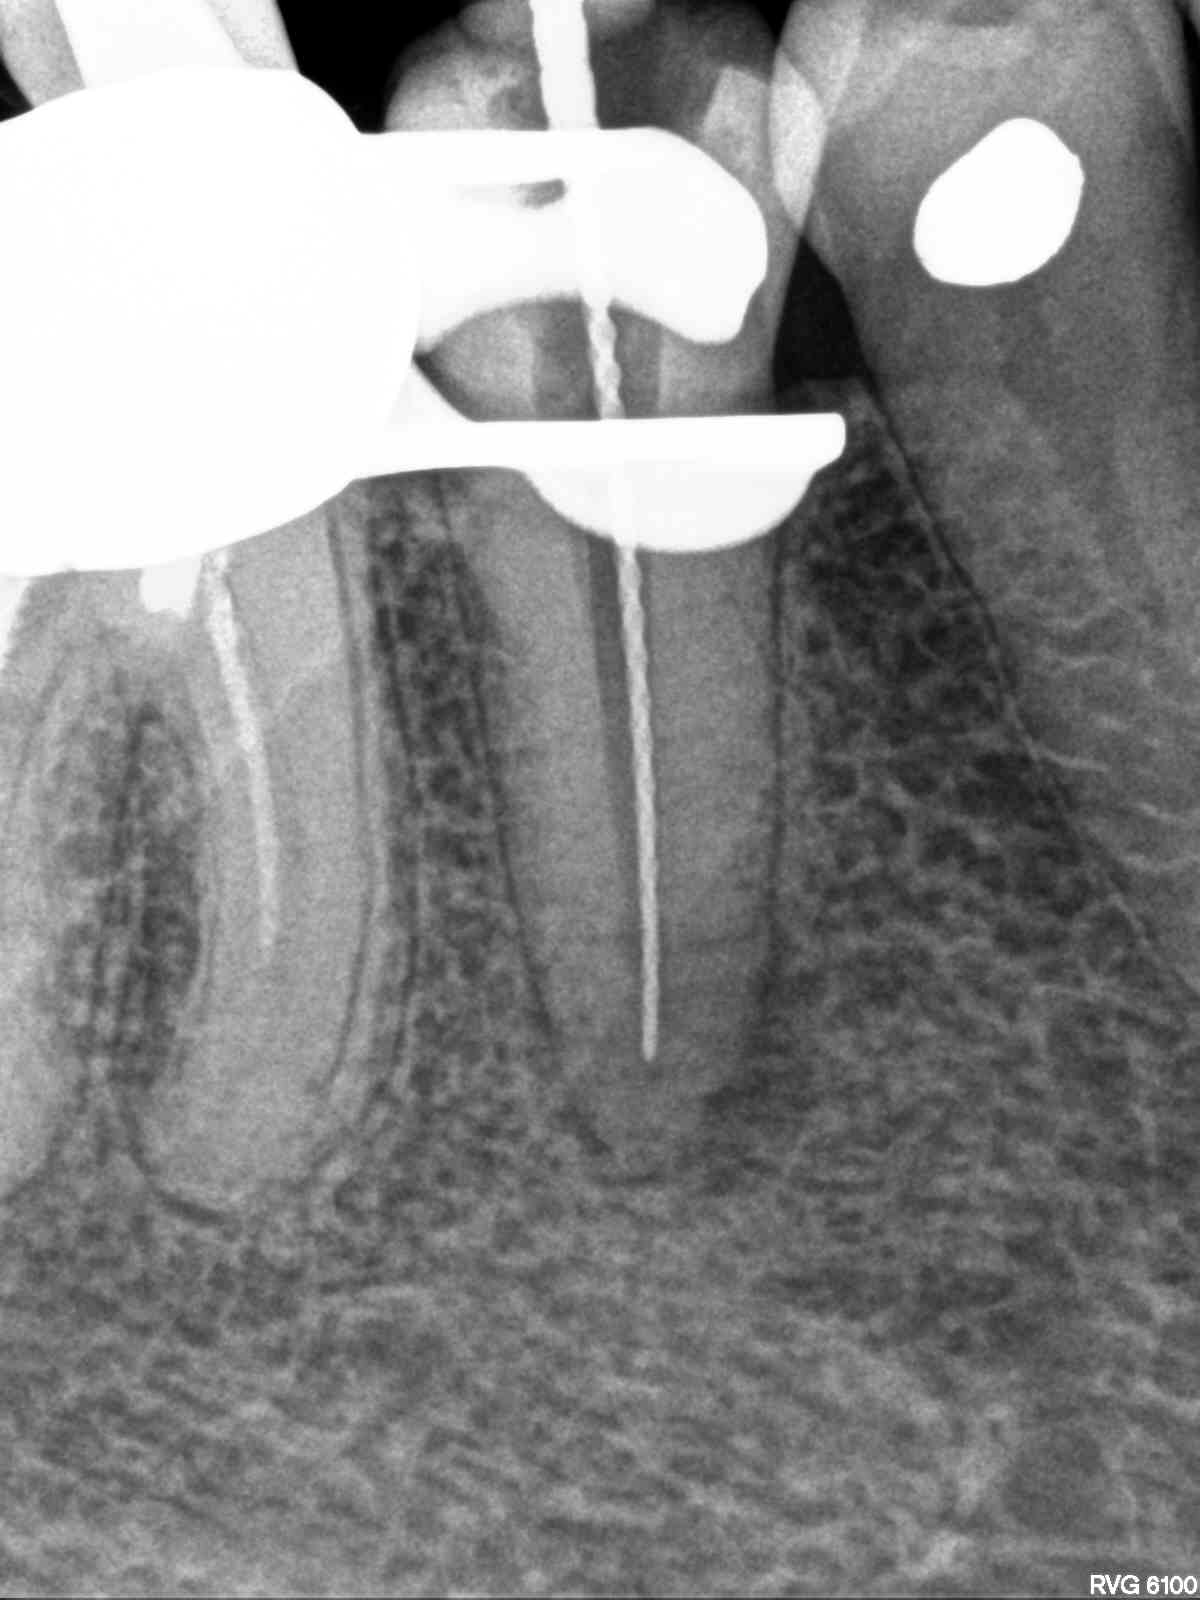

R13

1200 × 1600

Kurz oder lang? Das DVT kann helfen.